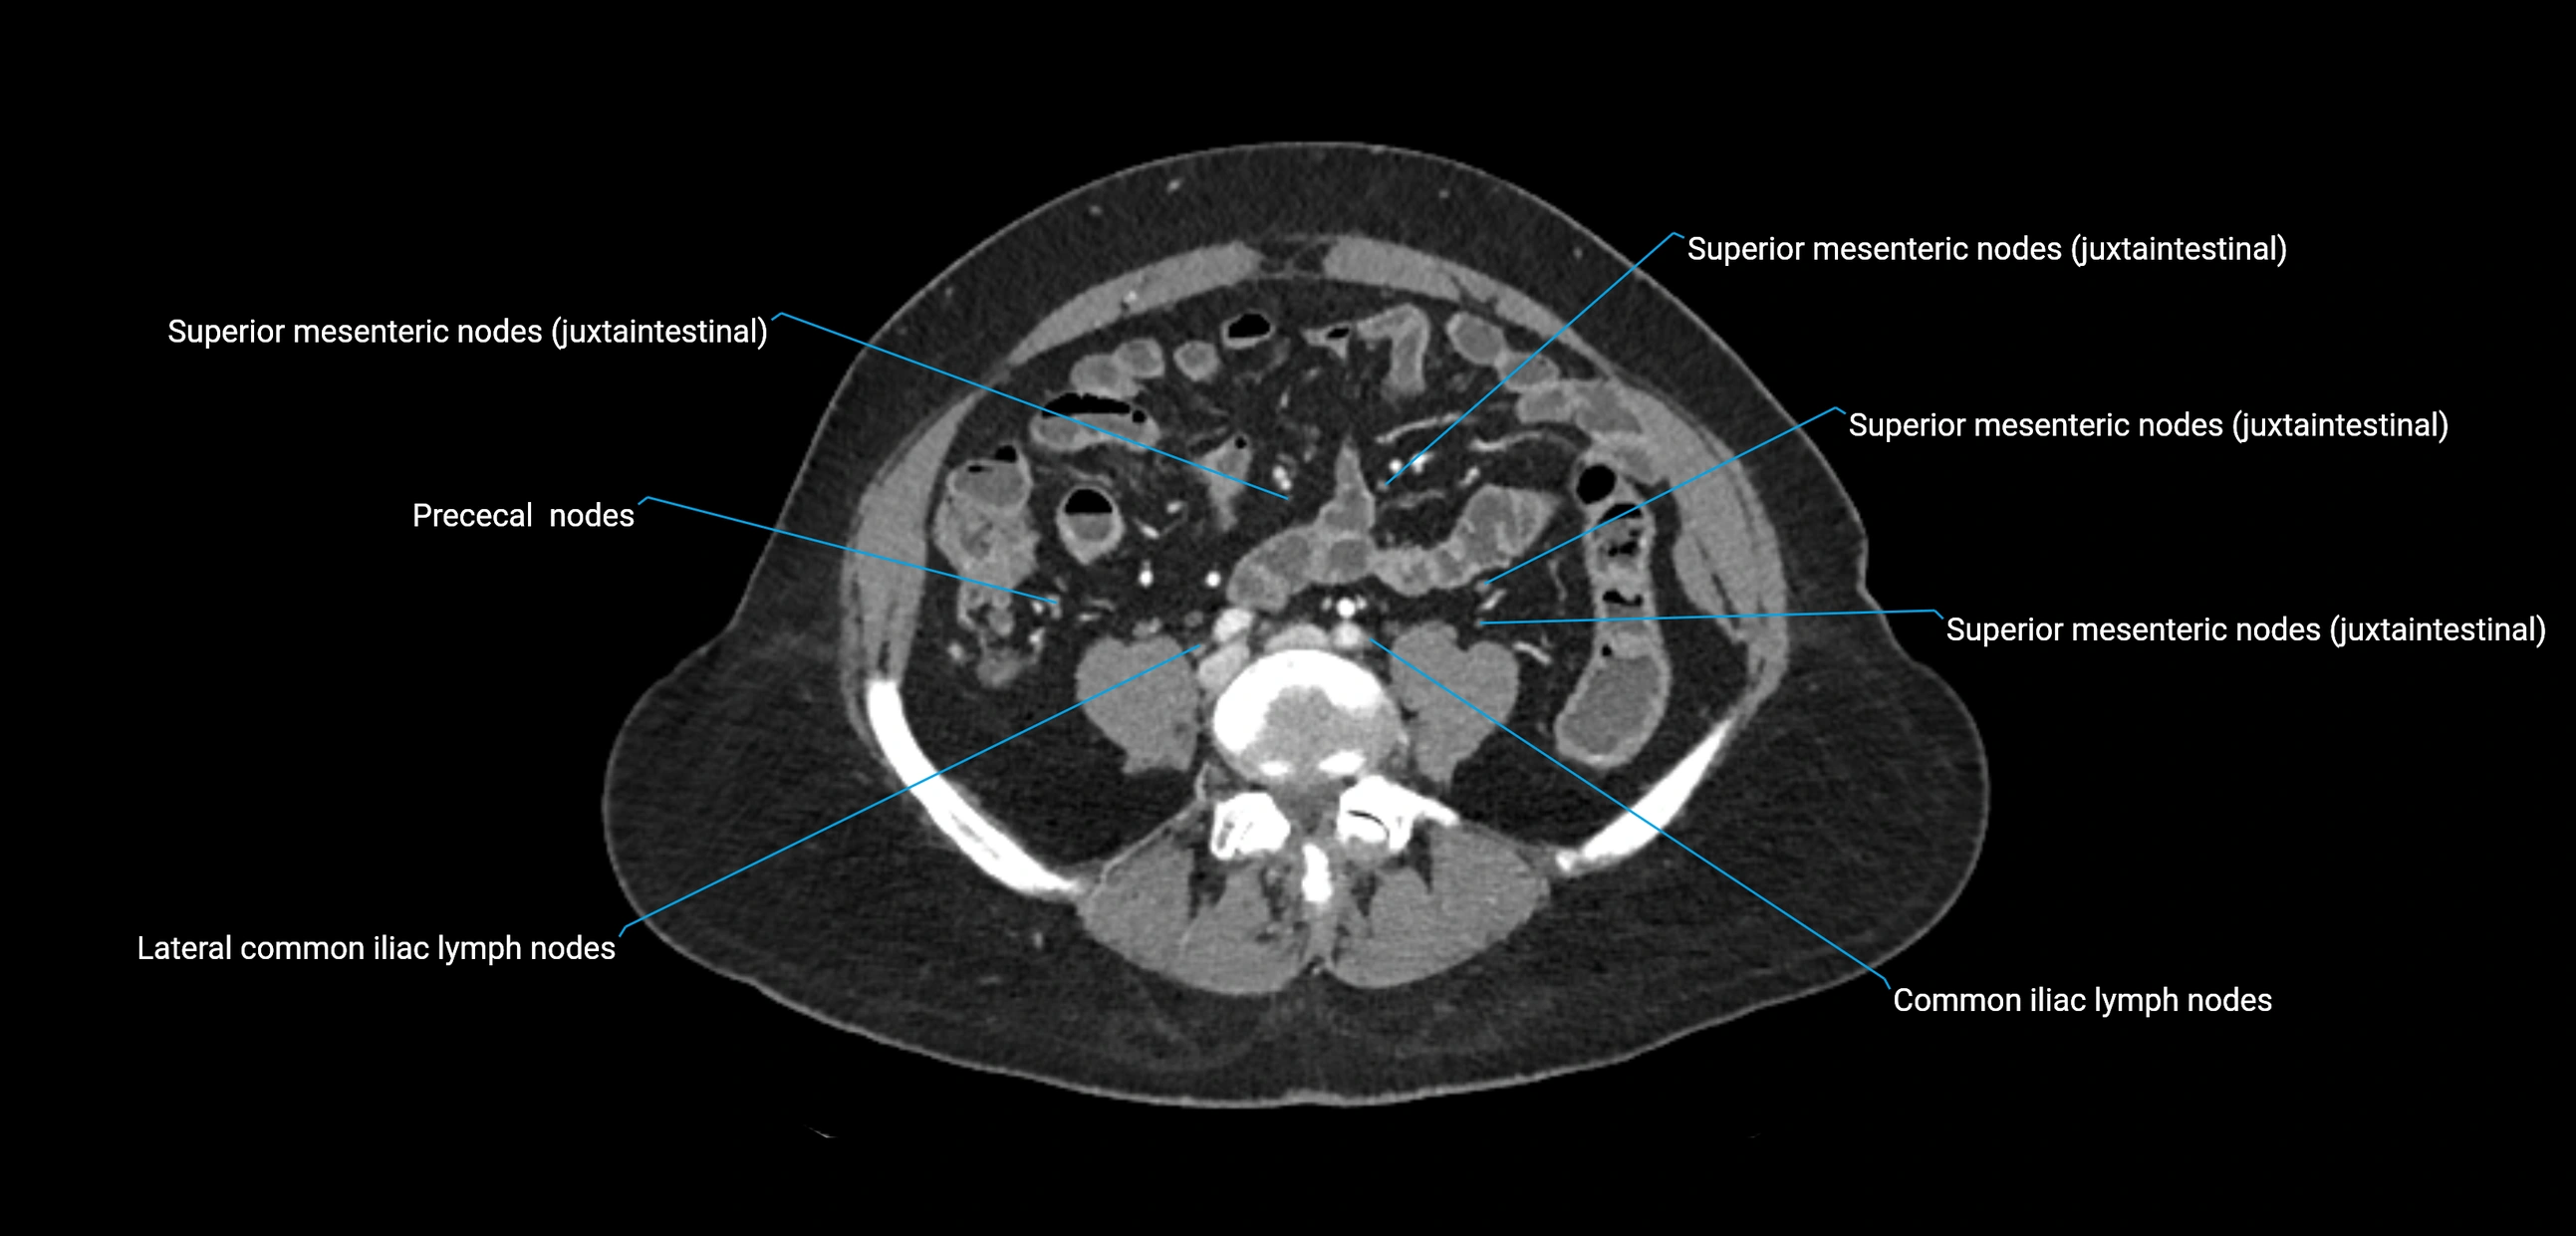

CT Appearance

CT Pre-Contrast:

• Nodes appear as soft-tissue density nodules adjacent to the aorta and IVC

• Calcification may be seen in chronic infections (e.g., tuberculosis)

CT Post-Contrast:

• Normal nodes enhance homogeneously

• Malignant nodes may show heterogeneous enhancement, central necrosis, or conglomerate formation

• Size >1 cm short axis is suspicious, though morphology and distribution are equally important